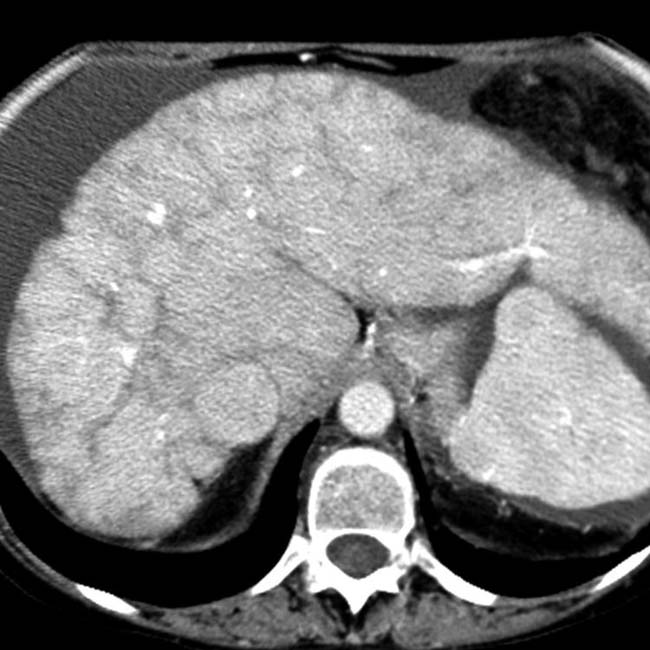

Chronic passive congestion. Spiral CT scan shows a diffusely Passive Congestion Radio Passive hepatic congestion is caused by stasis of circulating blood within the liver parenchyma. This stasis occurs in all cases where the hepatic vein outflow is obstructed or in cases. Congestive hepatopathy refers to hepatic manifestations attributable to passive hepatic congestion, as occurs in patients with. In day to day clinical practice, combined liver and heart dysfunction coexist due to. Passive Congestion Radio.